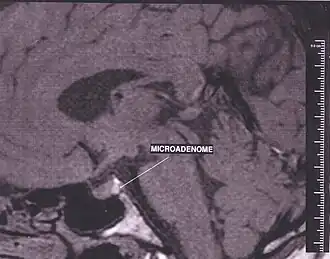

Лабораторная и инструментальная диагностика проводится по результатам исследования уровня АКТГ и подтверждения наличия микро или макроаденомы гипофиза, характеристики ее роста, оценки динамики роста аденомы в сравнении с периодом после двусторонней адреналэктомии до развития заболевания. Для кортикотропиномы в условиях удаленных надпочечников характерно повышение уровня АКГТ более 200 пг/мл, а также отсутствие циркадианного ритма секреции. Величина АКТГ отражает активность аденомы и соответствует выраженности гиперпигментации. При быстро растущих аденомах с инфильтративным ростом и резко выраженной гиперпигментацией уровень АКГТ способен достигать 3000 пг/мл и более.[8]

Оперативное вмешательство по поводу кортикотропиномы применяется как при микроаденомах, так и при опухолях больших размеров. Последнее время широко вошёл в клиническую практику метод хирургического вмешательства с трассфеноидальным доступом. Данная методика применяется при опухолях, растущих вниз. В случае большой инвазивной, растущей вверх аденомы гипофиза у пациентов с синдромом Нельсона используют трансфронтальный доступ. Результаты хирургического лечения при небольших опухолях лучше, чем при аденомах с распространённым ростом. Микрохирургическая техника обеспечивает в большинстве случаев полное удаление новообразования, однако после применения оперативного метода лечения встречаются рецидивы заболевания[1].